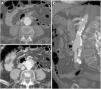

Varón de 54 años con esófago de Barrett que acude por cuadro de hemorragia digestiva alta con inestabilidad hemodinámica. Se realiza endoscopia en primera instancia que demuestra una lesión estenótica en tercio proximal del esófago que impide el paso del endoscopio. Ante nuevo episodio de inestabilidad se decide realizar tomografía computarizada basal y tras administración de contraste intravenoso (CIV) con adquisición bifásica (solo se muestra fase arterial). Corte axial (A) en el que se identifica un engrosamiento parietal esofágico (*) con infiltración serosa que oblitera el plano graso de separación con el cayado aórtico en relación con extensión tumoral. Las reconstrucciones MIP en planos axial (B) y sagital (C-F) demuestran extravasación activa de CIV desde el cayado aórtico hacia la luz esofágica (flecha).

Erosión del injerto en varón de 61 años con antecedente de bypass aortobifemoral que presenta fiebre de largo tiempo de evolución, escalofríos, debilidad y bacteriemia persistente. Ante la sospecha de infección del injerto se realiza TC con CIV en fase portal (A, B, C) que revela edema periinjerto y engrosamiento parietal de la tercera porción del duodeno (*) englobando la rama iliaca derecha del bypass en ausencia de plano graso de separación. La reconstrucción sagital (D) representa el nivel de los cortes axiales y la reconstrucción coronal (E) apoya los hallazgos descritos. No se objetiva extravasación de CIV. Se realiza SPECT con leucocitos marcados (F, G) que demuestra acúmulo de radiotrazador y PET-TC (H) que pone de manifiesto el incremento de la actividad metabólica en la región proximal del injerto, hallazgos sugestivos de infección. La cirugía (I) demostró la presencia de erosión del injerto (elipse discontinua).